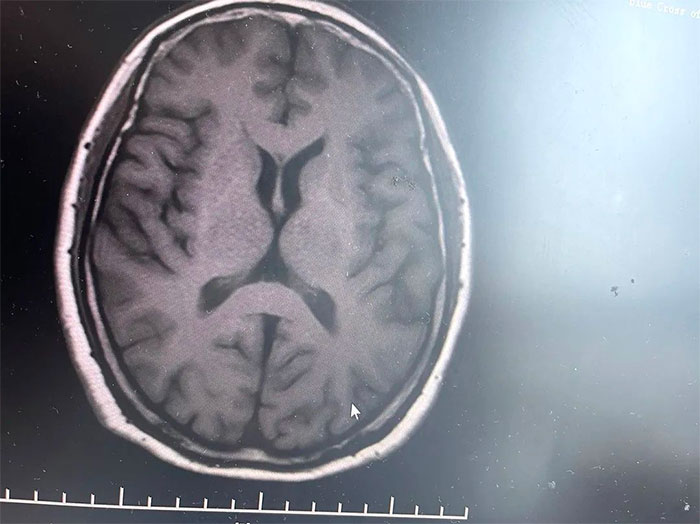

▲ MRI影像提示符合多系统萎缩表现

经磁共振(MRI)检查显示,林女士桥脑“十字征”、“壳核裂隙征”、“小脑萎缩”,符合多系统萎缩影像表现,再次验证了李振并主任的临床判断——多系统萎缩。